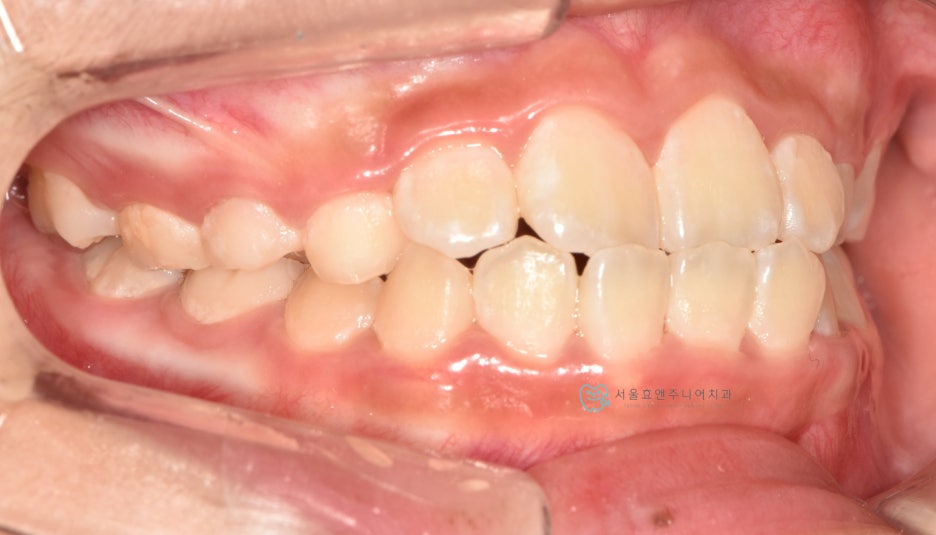

프리올소 착용 9개월 뒤

프리올소 착용 후 9개월 뒤 모습입니다. 앞니 반대교합이 수정되었습니다. 처음에 문제가 되고 있었던 아래앞니의 치은퇴축도 많이 개선되었습니다. 교합이 개선되어 치아의 위치가 바로잡히고, 치아에 무리한 힘을 더 이상 주지 않으니, 치은퇴축은 시간이 더 지나면서 점점 더 개선될 것으로 생각됩니다.